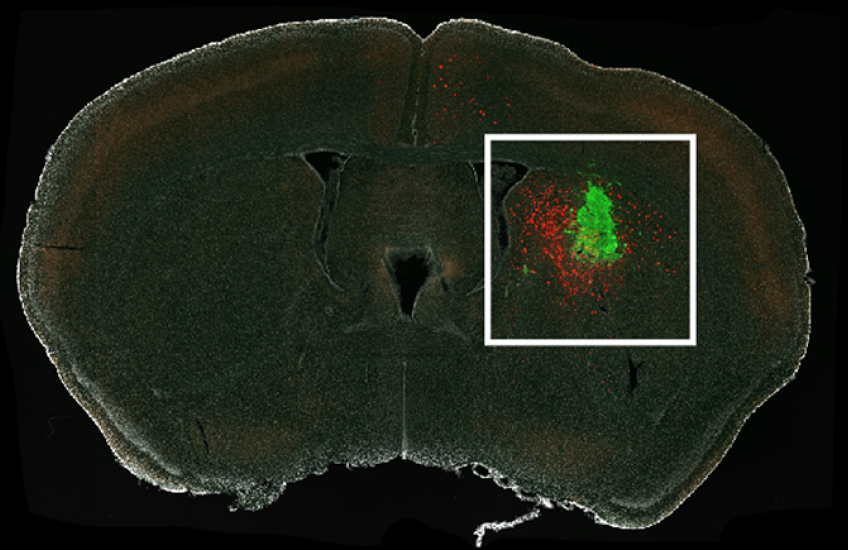

Now, she and HMS collaborators have filled in a piece of the puzzle by providing the first look at the types of neurons in the brain that connect to gliomas. Findings are reported Dec. 4 in PNAS.

Profiling the identities and properties of such glioma-innervating neurons in mice provides new insights into what drives the cancers’ formation and spread in the brain and how researchers might develop new treatment strategies to stop them from coming back.